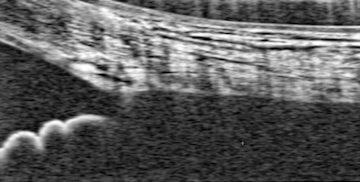

• Thick Prelaminar Tissue Decreases Lamina Cribrosa Visibility

• KA Lucy, B Wang, JS Schuman, RA Bilonick, Y Ling, L Kagemann, IA Sigal, I Grulkowski, JJ Liu, JG Fujimoto, H Ishikawa and G Wollstein

• Investigative Ophthalmology and Visual Science, 58(3), 1751-1757, March 2017.

image